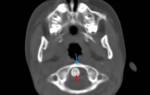

Для исключения перелома позвоночника назначают рентгенографию. В сомнительных случаях дополнительно проводят КТ или МРТ. При подозрении на неврологические нарушения пациента направляют к невропатологу или нейрохирургу. Лечение осуществляет врач-травматолог в травмпункте. Рекомендуется постельный режим. Для разгрузки позвоночника лучше спать на жесткой поверхности (можно подложить деревянный щит под матрас) с валиком под поясницей.

После этих мероприятий пациента срочно доставляют в травматологическое, нервное или нейрохирургическое отделение для обследования и лечения. План обследования включает рентгенографию позвоночника, неврологический осмотр, спинномозговую пункцию, МРТ и миелографию. Лечение проводится в стационаре.